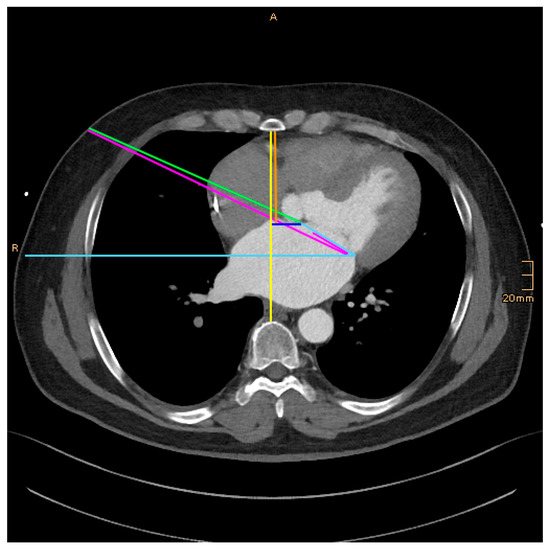

The following morphological parameter data were measured and collected retrospectively (Figure 1, Figure 2 and Figure 3):

DSS–Distance between the sternum and the spine: On an axial image, at the level of the midportion of the mitral valve.

DSM–Distance between the sternum and the anterior annulus (A2) of the mitral valve: On an axial image, at the level of the midportion of the mitral valve.

DSA–Distance between the sternum and aorta: On an axial image, just above the right atrial appendage.

DNM–Distance between the nipple and the anterior mitral anulus: From an axial image view, the distance between the nipple as the entering point of the thorax and the anterior mitral anulus was measured. In female patients, the expected entering point through the fourth intercostal space with the tissue above was taken.

DVM–Distance to the left between the vertical and the anterior mitral anulus (DVM): From an axial image view, at the level of the midportion of the mitral valve, the distance between the vertical line of the DSS measurement and the anterior mitral anulus was measured. This is a parameter reflecting how far left the mitral valve is located in the thorax.

AMH–Angle between the mitral valve and the horizontal: From an axial image view, the angle between the mitral valve and the horizontal was measured. The plain of the mitral valve was defined by the connection line between the anterior and posterior anulus at the midportion (corresponding to A2, P2 segment) of the valve.

ANM–Angle between the mitral plane and the line from the working port to the mitral valve: From an axial image view, the angle between the mitral plane and the line from the working port to the mitral valve was measured.

Figure 1. Measurements. DSS–Distance between the sternum and the spine: yellow. DSM–Distance between the sternum and the anterior annulus (A2) of the mitral valve: orange. DNM–Distance between the nipple and the anterior mitral anulus: green. DVM–Distance to the left between the vertical and the anterior mitral anulus (DVM): dark blue. AMH–Angle between the mitral valve and the horizontal: light blue. ANM–Angle between the mitral plane and the line from the working port to the mitral valve: magenta.